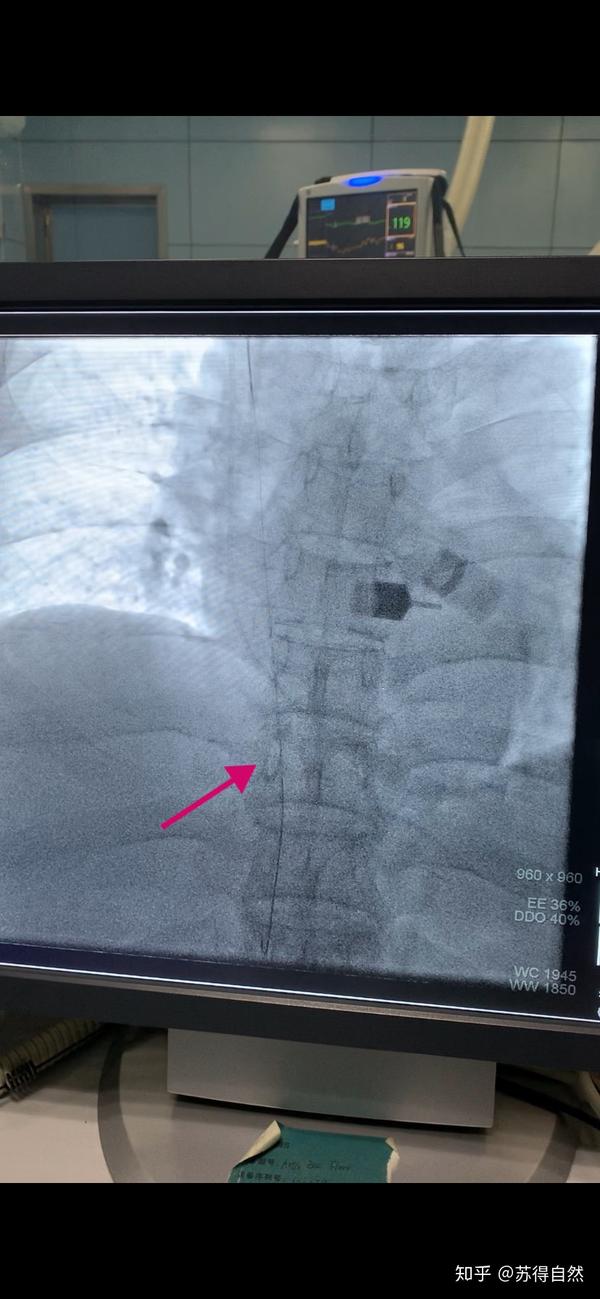

造影提示:右无名静脉全程闭塞.

右侧无名静脉闭塞的修复-牵张导丝技术的运用